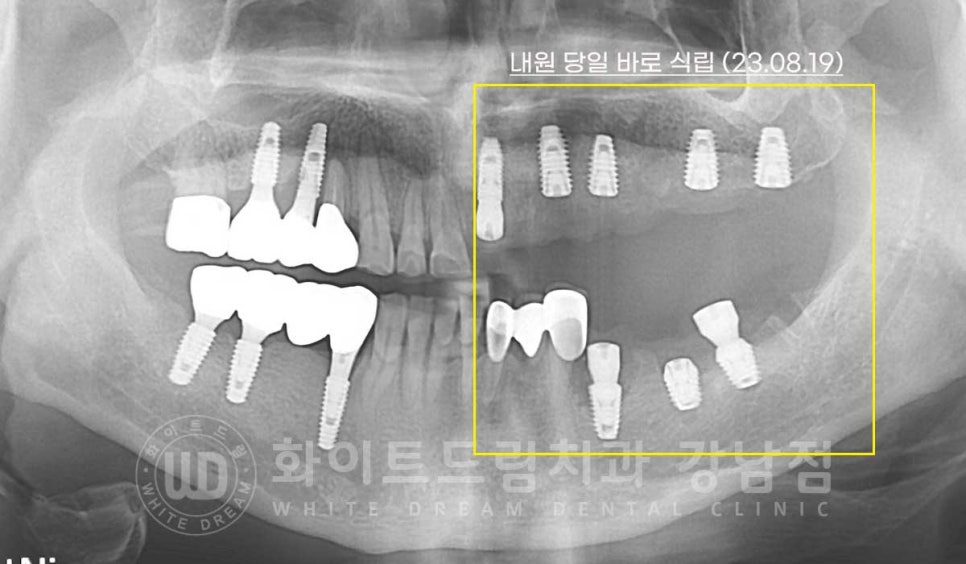

환자분의 초진 구내 사진입니다.

현재 임플란트가 식립되어 있는 10번대 어금니, 30번대 어금니 부위에

심한 염증과 골소실이 일어나 있는 상태입니다.

이 외에도 치주염으로 20번대 브릿지 부위의 상태도 굉장히 좋지 못한 상태인데

임플란트의 상태부터 자세히 보겠습니다.

임플란트 재수술의 주원인 / 찢어짐 & 주위염

10번대 어금니 부위는 임플란트가 찢어지면서 주위 염증이 생겨있고

40번대 어금니는 임플란트 주위염으로

증상은 모두 '임플란트 흔들림'이 발생하고 있는데요.

내원 횟수를 줄이기 위해 내원 당일 보철과 임플란트를 제거한 후 바로 임플란트 식립을 진행합니다.

수술일자 : 23.08.19